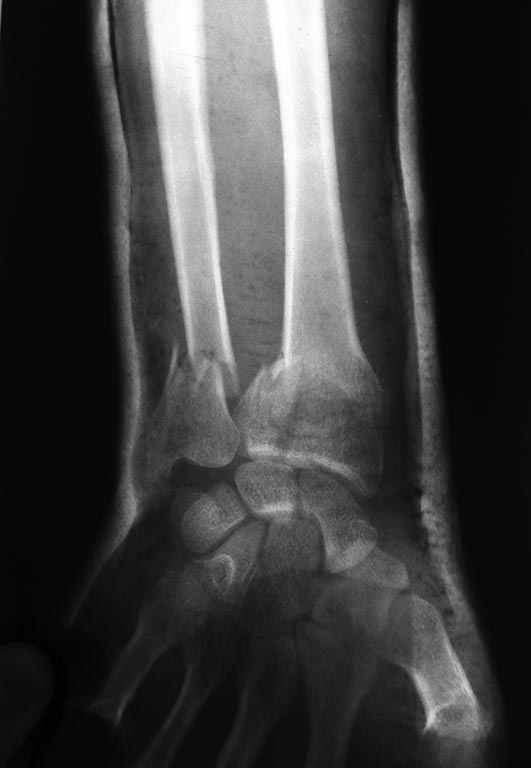

Р-грамма после репозиции.